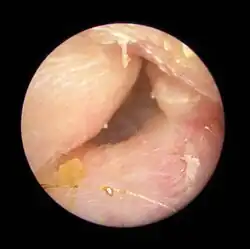

| Exostoses in the ear canal, as seen through otoscopy | |

Surfer's ear is the common name for an exostosis or abnormal bone growth within the ear canal. They are otherwise benign hyperplasias (growths) of the tympanic bone thought to be caused by frequent cold-water exposure.[1] Cases are often asymptomatic.[1] Surfer's ear is not the same as swimmer's ear, although infection can result as a side effect.

-

Exostosis in ear canal -

Exostosis in ear canal